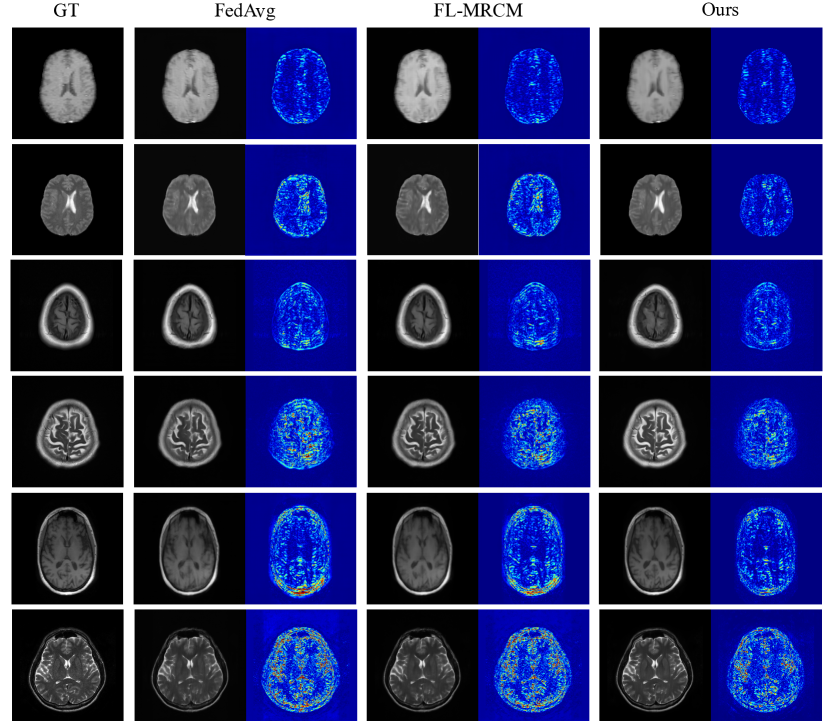

Refer to caption

Figure 4: Qualitative results of different methods when training with T1/T2-weighted B, F, I as local data and testing on T1 B, T2 B, T1 F, T2 F, T1 I, T2 I test set respectively. The second column of each sub-figure is the error map (absolute difference) between the reconstructed images and the ground truth.

Second, we compare the performance with the prior arts [64] when taking T1/T2-weighted images from B, F, and I as local data and unlabeled T1/T2-weighted images of OASIS-3 as public data. The results are reported on the corresponding test sets of local data, respectively. From Table 7 we can see that, when compared with the prior art [64], our method achieves very competitive reconstruction performance in terms of SSIM and PSNR with higher communication efficiency while at the same time maintaining the local data privacy by not sharing local model parameters/gradients or any product inferred from local private local data. The counterpart [64] not only iteratively shares local model parameters but also shares the features inferred on each local private data. Besides the superior guarantees w.r.t. data privacy, our method demonstrates higher communication efficiency through lower bandwidth and higher flexibility (offline communication without any synchronization requirements on the local model). Notably, when testing on T2-weighted F and I, we achieved better performance than centralized training (collecting local data together for training), e.g., on T2-weighted F, we achieved 0.9374/32.76 SSIM/PSNR over the 0.9002/30.47 SSIM/PSNR of centralized training. The reason is that we utilize additional unlabeled, non-sensitive, cross-domain public data, which, we assume, are easily acquired in real-world clinical scenarios. Comparisons of qualitative results are shown in Figure 4.